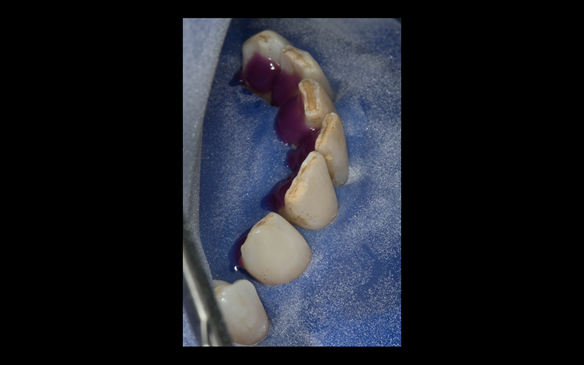

- The remaining maxillary teeth had hopeless prognosis in the short term. They exhibited 80 - 100% alveolar bone loss with increased mobility (Grade 2 - 3).

- The lower right second premolar and lower left first premolar (LR5 LL4) had hopeless prognosis in the short term. They exhibited 80 - 100% alveolar bone loss with grade 3 mobility.

- Extraction of all upper teeth and LR5 and LL4 and fitting of immediate acrylic based (Mk 1) dentures - complete upper and lower partial